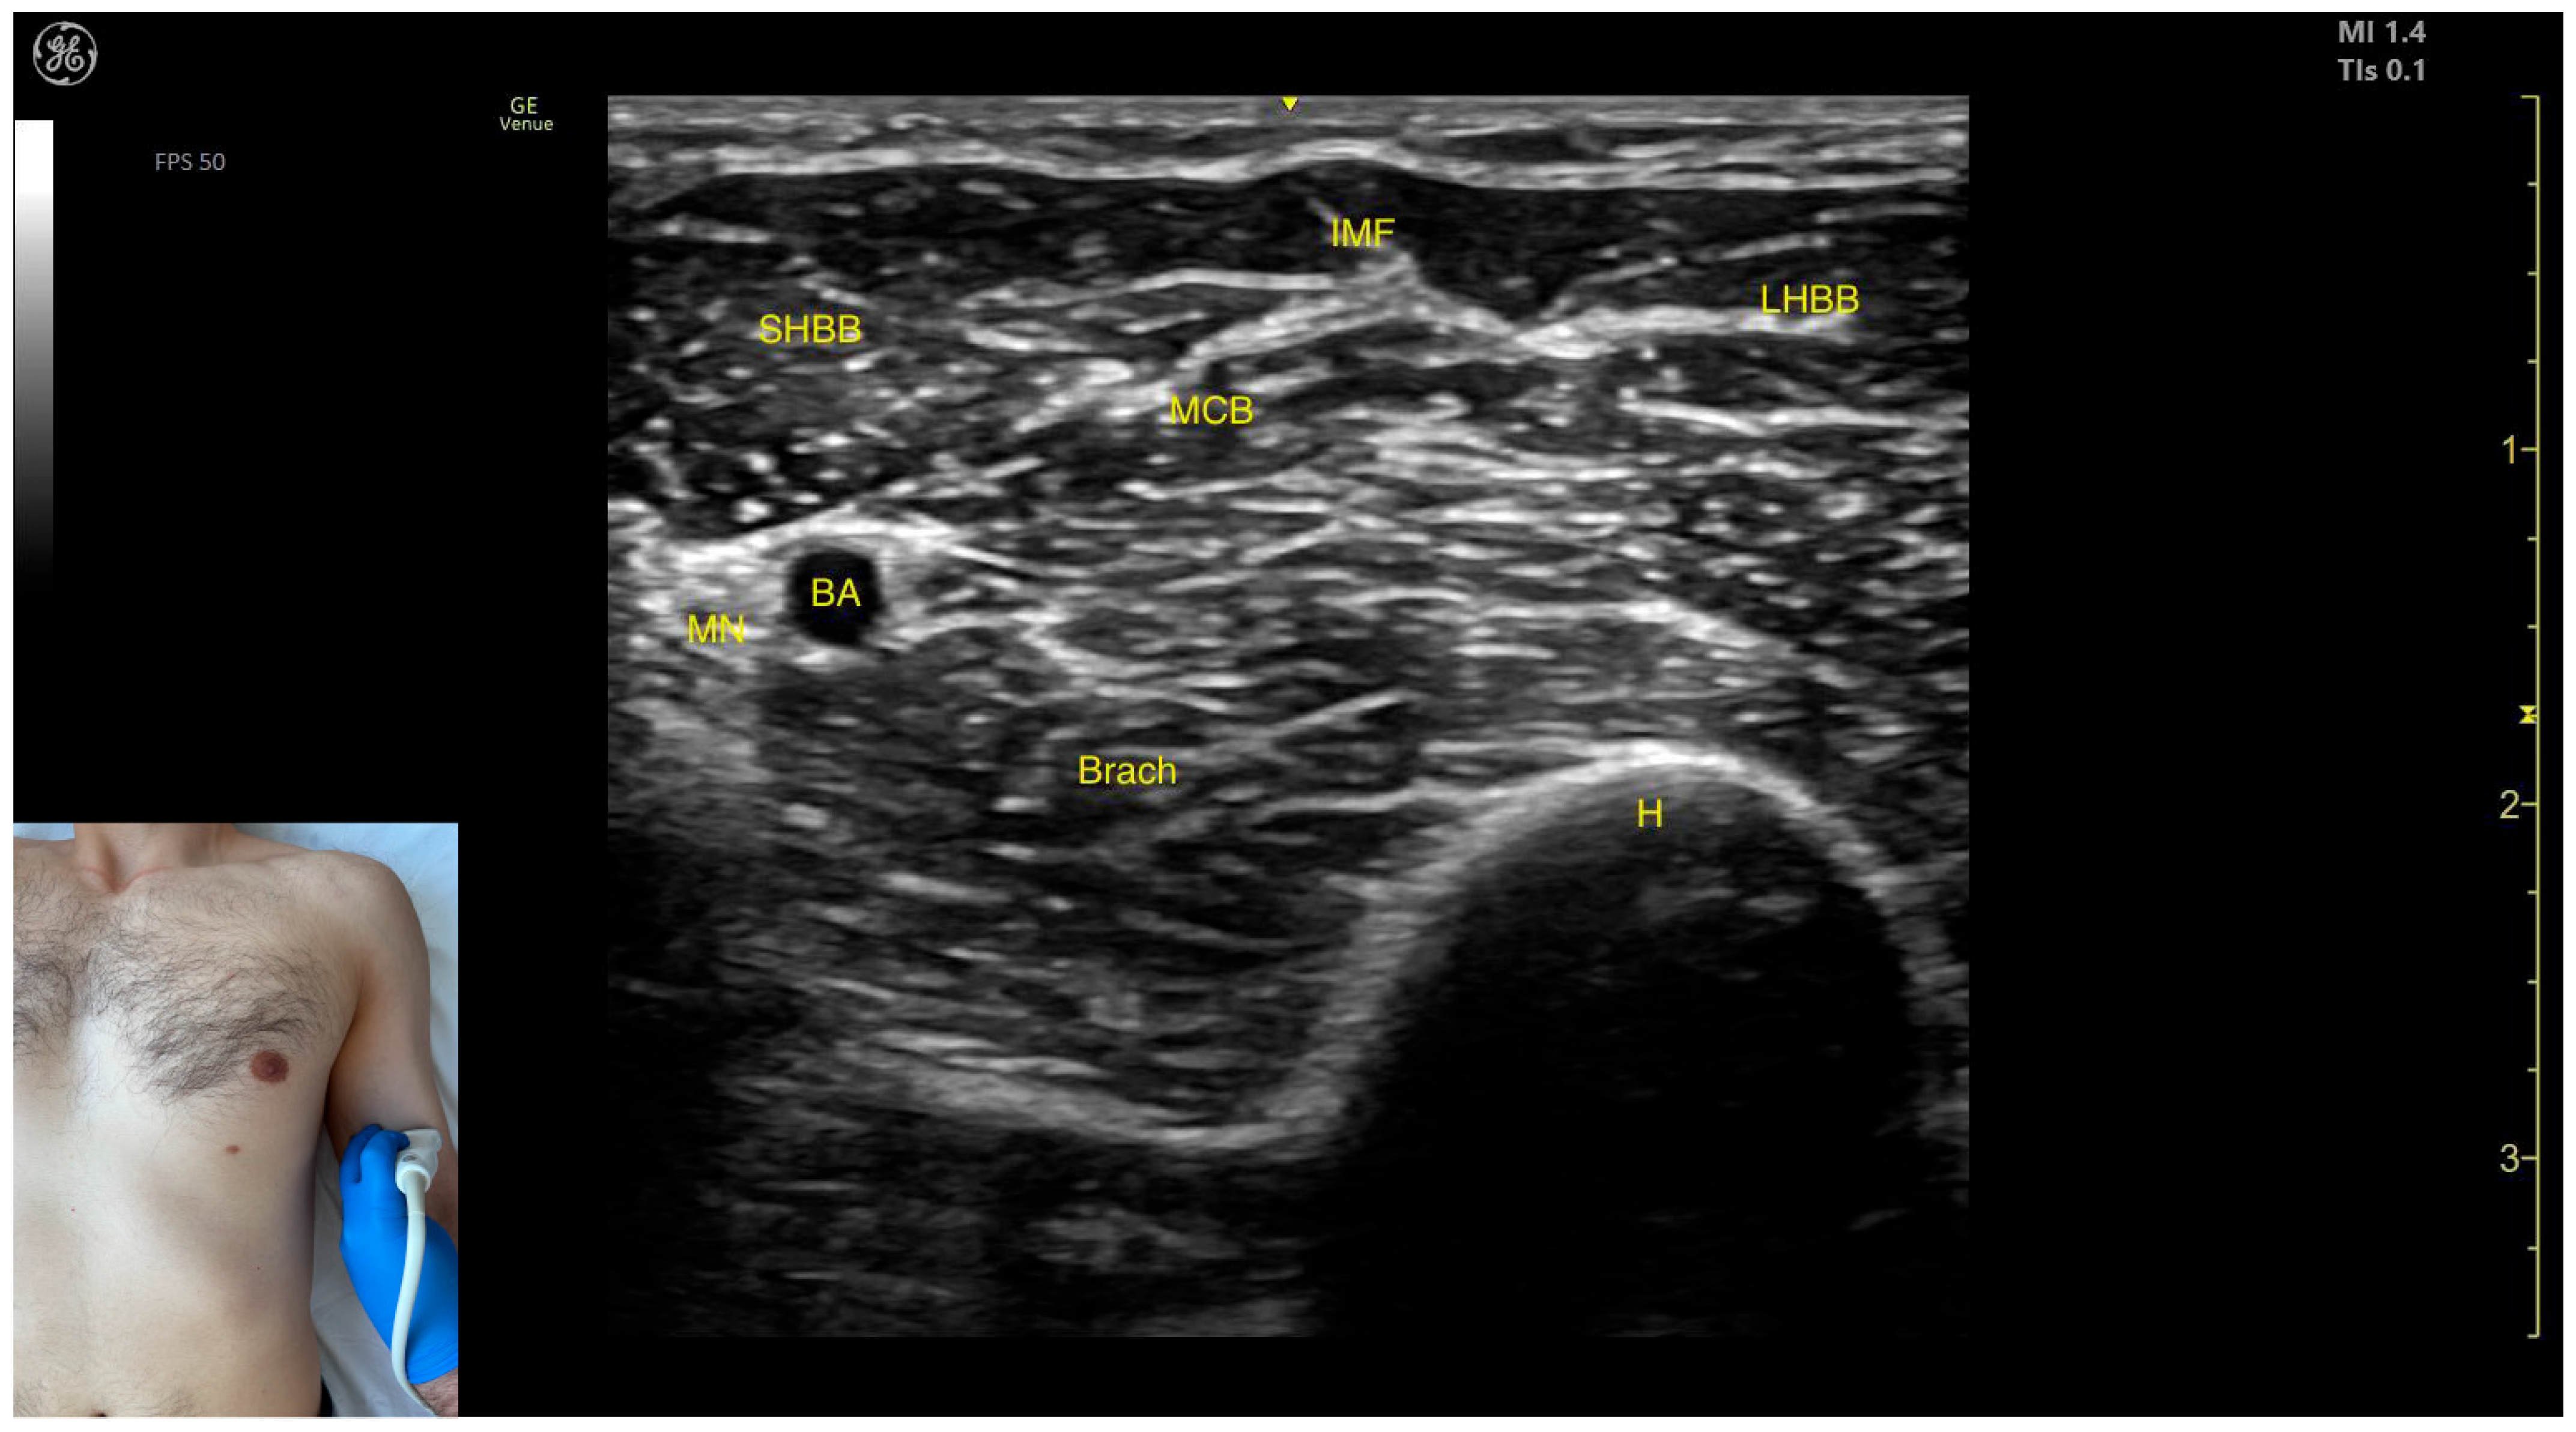

- Muscle position: It represents the most superficial muscle mass of the anterior arm at this level [57].

- Muscle morphology: It has two heads, with the long head (LHBB) located laterally and the short head (SHBB) positioned medially, separated by an intramuscular fascia that allows them to be individually targeted during procedures.

- Innervation and vascular supply: In the depth of the muscle at the level of the bicipital fossa (medial portion), the brachial artery is observed laterally, while the median nerve is located medially to the artery, with the bicipital fossa representing a longitudinal groove bordered anteriorly by the BB and brachialis muscles and posteriorly by the medial head of the triceps brachii.

- External fascia: The BB lacks a pronounced fascia that separates it from the brachialis, which is relevant when performing BoNT-A injections.

- Dynamic evaluation: During dynamic evaluation (Video S1), proximal scanning toward the shoulder joint reveals a decrease in the size of the brachialis muscle until it transforms into a tendon at the mid-arm level, where the insertion of the coracobrachialis (CB) muscle on the humerus can be observed deep to the BB. Scanning further toward the proximal third of the arm shows the inversion of the positions of the median nerve and brachial artery within the bicipital fossa [57]. Continuing the scan proximally toward the shoulder joint reveals an increase in the size of the CB muscle in the medial portion of the arm. The musculocutaneous nerve is usually seen piercing the coracobrachialis before descending in the intermuscular fascia (IF) between the BB and brachialis. The CB muscle is not injected with BoNT-A due to its minor role as a weak flexor of the arm at the shoulder joint. The musculocutaneous nerve is targeted during diagnostic nerve block procedures to differentiate between spasticity and rigidity in cases where severe spasticity restricts elbow flexion or extension. Branches of the musculocutaneous nerve can be visualized via US on the anterior surface of the BB, appearing prominently and potentially being mistaken for intramuscular fascia [58]. The contraction of the BB can be observed during flexion maneuvers of the elbow and shoulder joints. With the elbow flexed at 90 degrees, performing forearm supination shows the BB gliding over the underlying brachialis muscle (Video S2) [12,55].